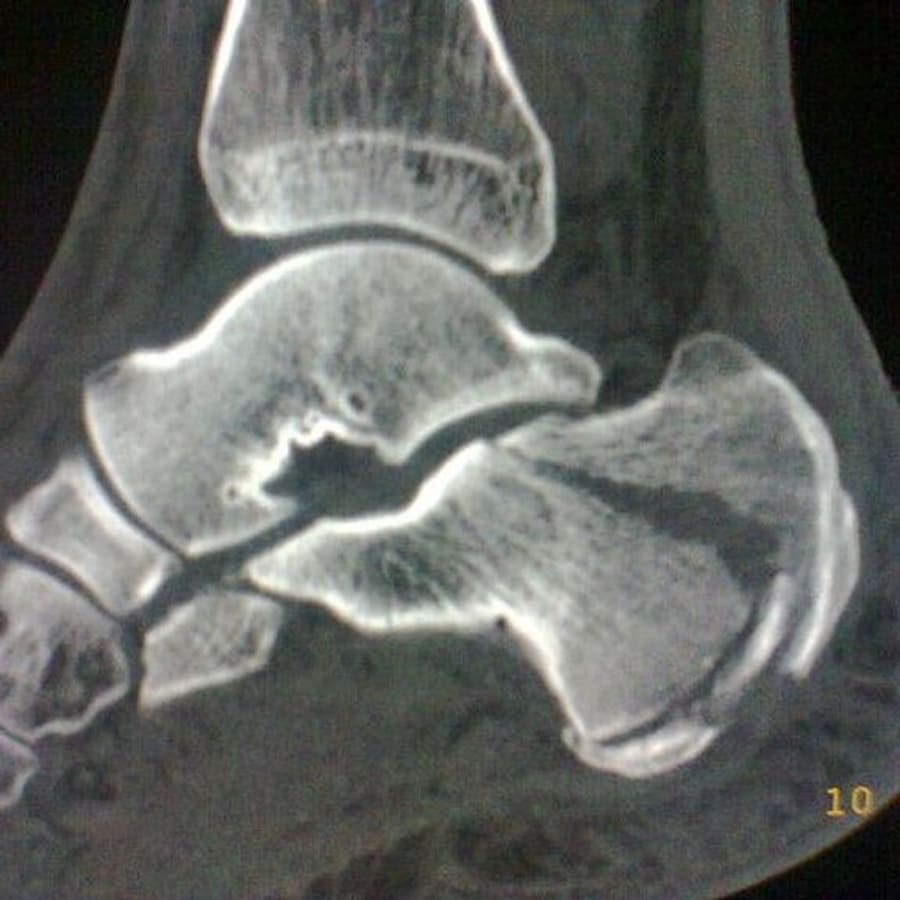

Como a microfratura óssea é diagnosticada?

O diagnóstico geralmente inclui a avaliação clínica com ortopedista e exame físico detalhado. Também é necessário realizar radiografias iniciais e/ou ressonância magnética (o exame mais sensível para microfraturas), para confirmar o diagnóstico e determinar o protocolo de tratamento mais indicado para cada caso.